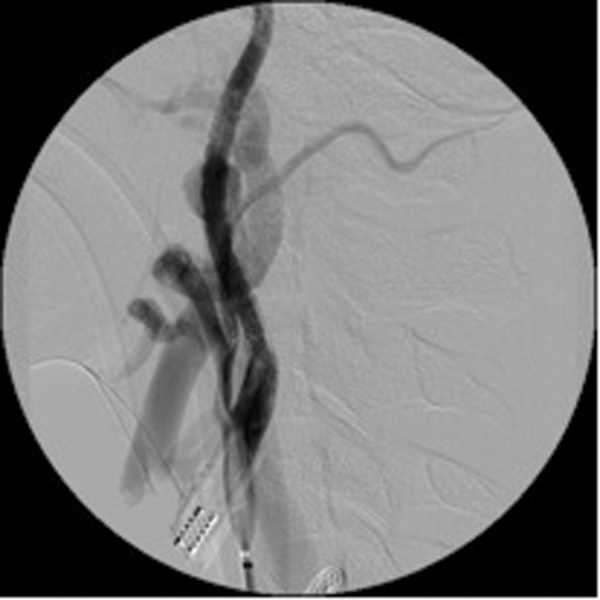

Detachable balloons, particles and / or sclerosants, and stents are used in the endovascular treatment of these lesions. (Figure 3 shows a case of a traumatic external carotid-jugular AV fistula treated by coil embolisation).

Figure 3: ECA- jugular fistula before and after embolisation.